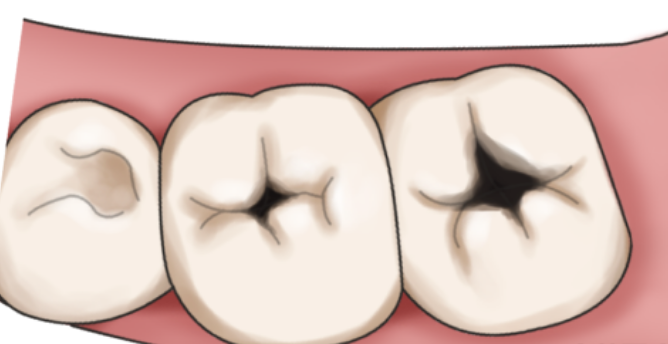

邻面龋齿:牙齿邻面发生龋坏未及时修补,龋洞可能导致牙齿邻接面破坏,形成明显缝隙。

食物嵌塞 → 牙龈发炎 → 牙缝再变大 →

更多食物嵌塞,形成一个恶性循环。